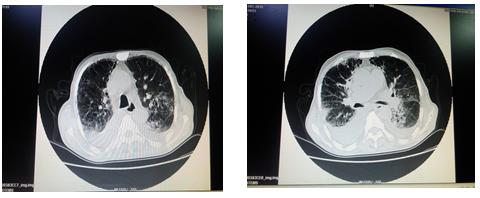

胸部CT:1.两肺间质性病变、间质纤维化可能;2.两侧胸腔积液,两侧胸膜肥厚粘连;3.肺门区及纵膈淋巴结增大,局部钙化;4.主动脉迂曲,主动脉壁钙化,心脏饱满;5.心包积液可能;6.考虑肝顶部钙化燥或胆管结石可能;7.所示胸部骨质改变,结合病史,考虑转移瘤可能。

以下是病人入院胸部CT: